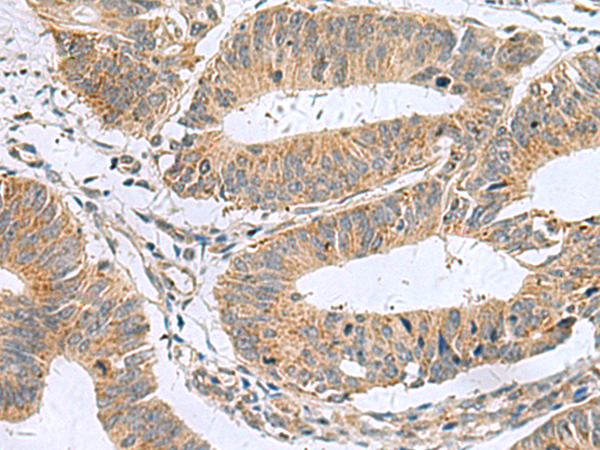

IHC positive control: |

Human colorectal cancer |

IHC Recommend dilution: |

50-100 |